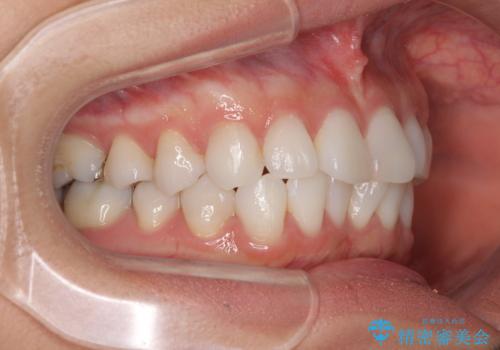

- 前歯のデコボコを気にして来院された患者様です。

海外に留学をされており、卒業後はしばらく日本にいるものの、再び就職のため出国するとのことでした。

定期的に日本に戻ってくる予定であるため、来院頻度の少ないインビザラインにて矯正治療を行うこととしました。

歯列不正が軽度であり、インビザラインの装着時間を遵守してくださったため、日本と海外を行き来しながらも2年弱でしっかりと仕上げることができました。